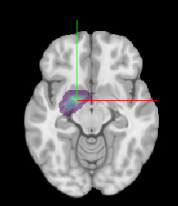

基于多重扩散模型和相关扩散指标检测系统性红斑狼疮患者脑白质微结构改变

Zhenxing Li, Huanhuan Li, Bailing Tian, Huiyang Liu, Yueluan Jiang, Pingting Yang, Guoguang Fan, Hu Liu. Detection of white matter microstructural changes in patients with systemic lupus erythematosus based on multiple diffusion models and related diffusion metrics.[J]. Neural Regeneration Research, 2026, 21(6): 2467-2474.  doi: 10.4103/NRR.NRR-D-25-00730